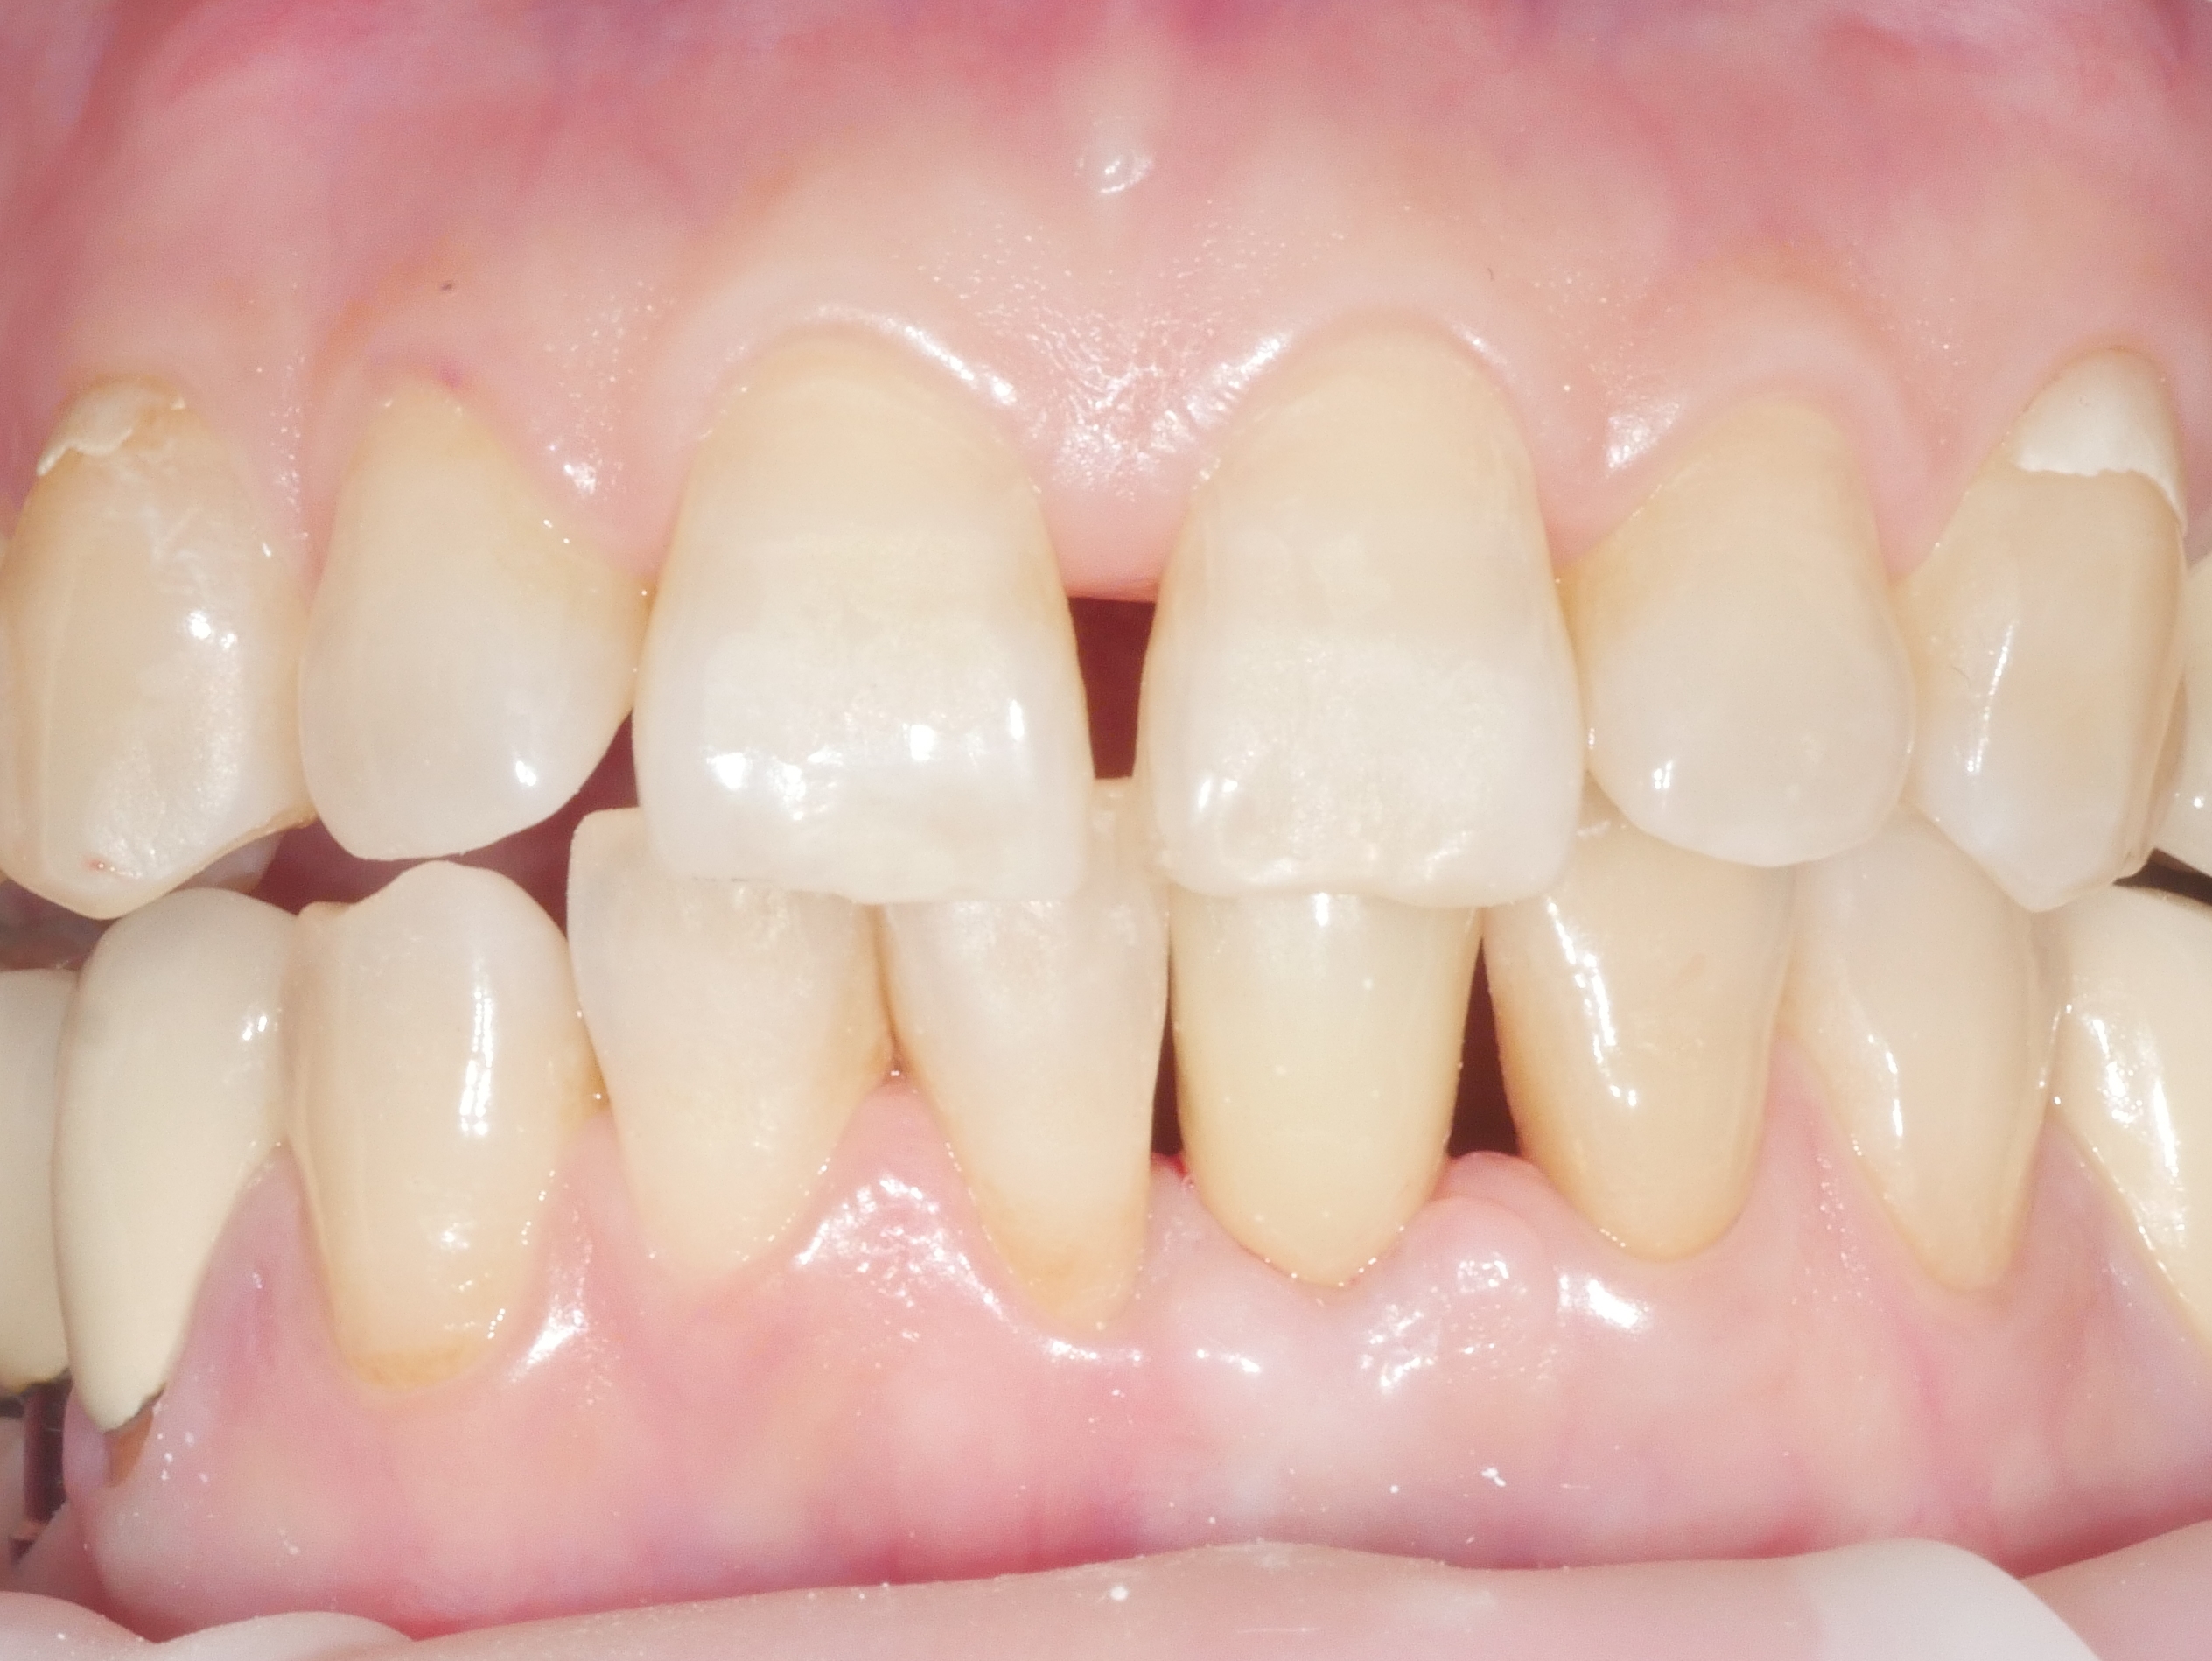

아래 앞니 빠진 부위를 임플란트로 치료

치료전 2025.04.15 / 치료후 2025.09.23